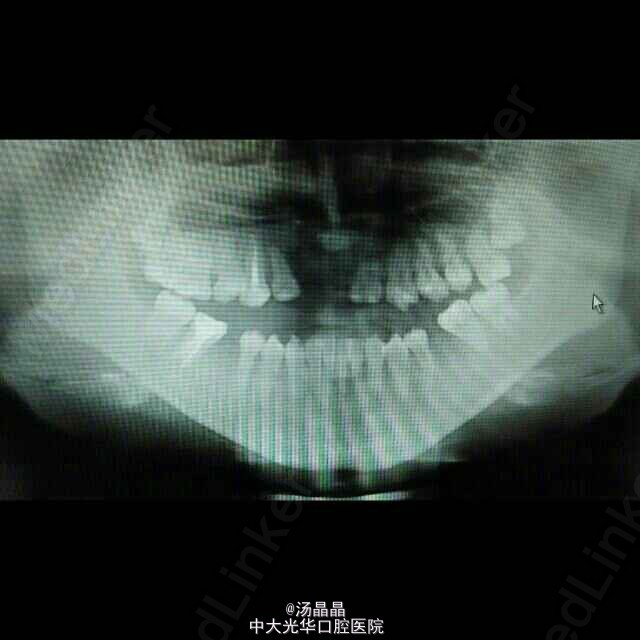

患者青年女性,上颌后缩,下颌前突6年,随发育渐进加重

面下三分之一长面型,侧面严重凹面型,上颌后缩,下颌前突,双侧颞下颌动度一致,无压痛,未闻及弹响和杂音,全口牙齿见正畸托槽,16.11.21.25.36.46缺失,中线齐,全牙弓反合,反覆盖大于3cm